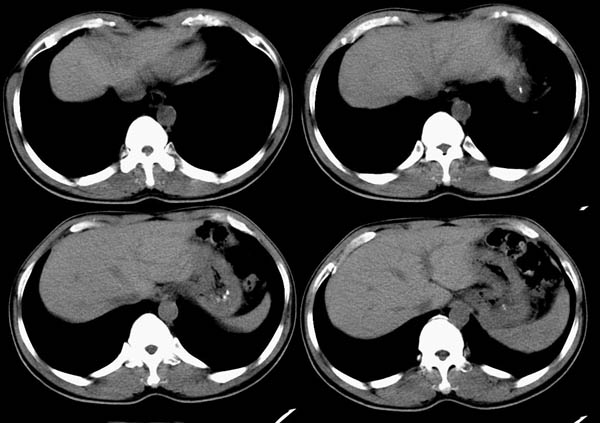

m50y以腹疼、腹胀2小时就诊。腹透肠胀气较明显,余无明显异常。做ct时腹疼已明显缓解;病人否认外伤史,否认血液病变、否认肝炎史。建议第二天做ct增强,病人第二天放弃了增强。脾脏区较高密度影ct值为60hu,正常脾脏ct值为45hu(窗宽:150,窗位:56)。

脾区病变局部2mm重建:

ct表现:脾脏内见较高密度影ct值为60hu,正常脾脏ct值为45hu(窗宽:150,窗位:56)。 边界清晰,周围见略低密度影

脾脏实质内高密度病变,ct值为60hu,边界清晰,无明显外伤病史,腹痛、腹胀2小时就诊,首先考虑脾脏血管瘤破裂出血。